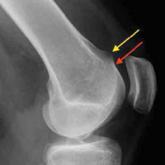

ArticleThe Effect of Ligament Injuries on Outcomes of Operatively Treated Distal Radius FracturesAuthor:Peter Tang, MD, MPHPublish date: January 26, 2017Various authors have documented wrist ligament injuries in patients with distal radius fractures (DRFs). We conducted a study to determine whether ...Read More